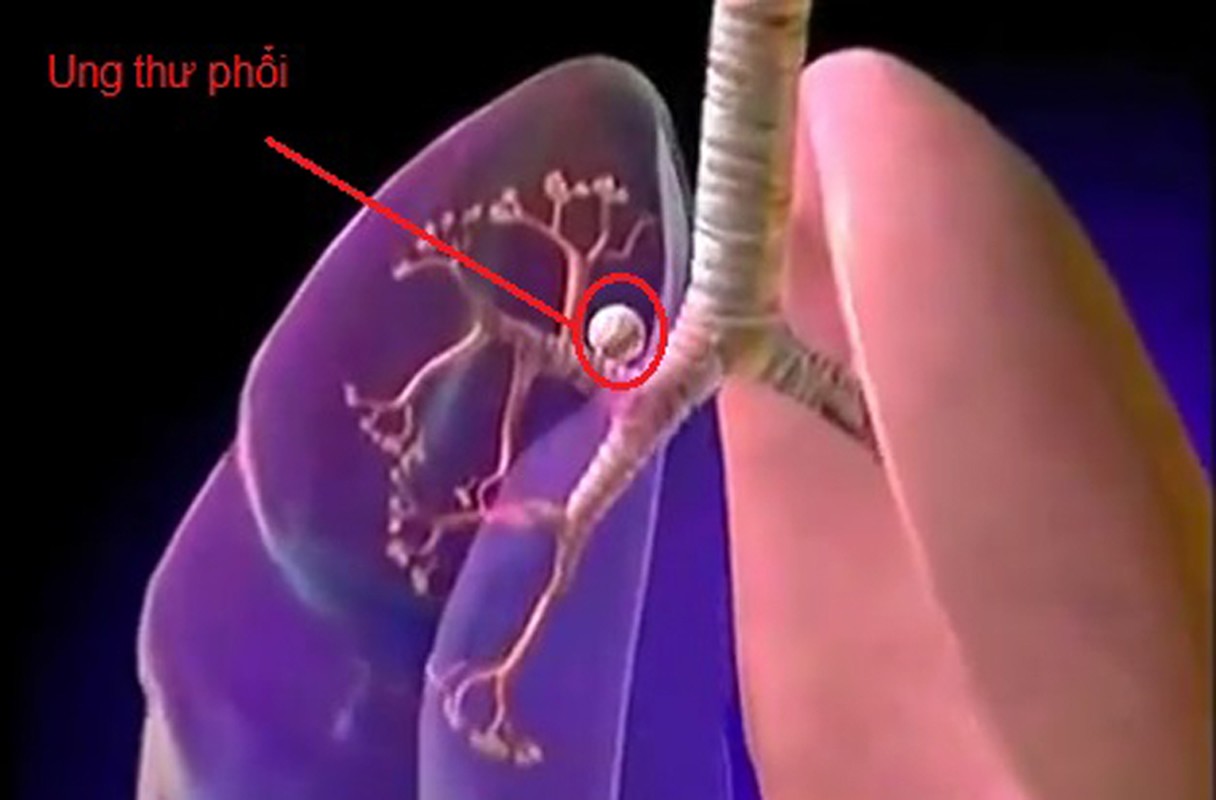

Đặc biệt, cryptoxanthin trong khoai môn giúp ngăn ngừa ung thư phổi và ung thư miệng hiệu quả.Ngoài công dụng ngăn ngừa ung thư, khoai môn có khả năng điều hòa huyết áp - lượng đường trong máu; chữa tiểu đường; thận và các bệnh về viêm khớp, u hạch. Để tận dụng lợi ích sức khỏe từ khoai môn, bạn có thể giải nhiệt với kem khoai môn. Chè khoai môn.

Đặc biệt, cryptoxanthin trong khoai môn giúp ngăn ngừa ung thư phổi và ung thư miệng hiệu quả.